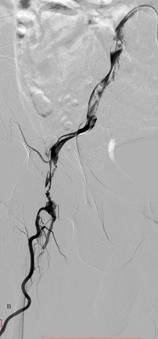

图1 患者男,46岁,胸痛5小时急诊入院,诊断为主动脉夹层(Standford B型),入院1周后行主动脉夹层腔内修复术,术后1周临床治愈出院。A为治疗前造影,B为覆膜支架修复破裂口后。